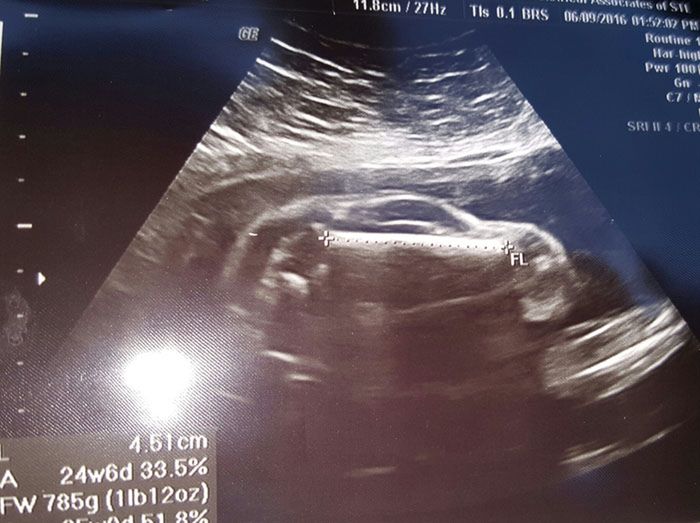

To, co ukazało się podczas badania USG wydaje się być bardzo dziwne. Z pewnością to zwykły przypadek lub wytwór wyobraźni, ale wyraźnie widać, że kobieta w brzuchu nosi coś w kształcie... samochodu!

Na szczęście młodego ojca nie opuszcza dobry humor. Pod burzliwą dyskusją, jaką wywołał jego wpis na Reddicie napisał, że skoro wygląda jak samochód, to musi to być chłopiec.